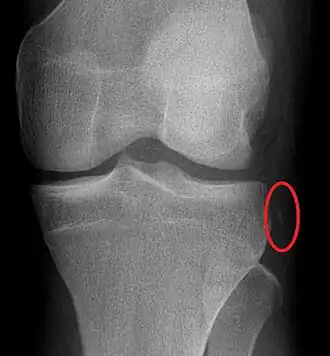

À la radiographie de face[6], la fracture de Segond présente une pastille d’os d’une taille caractéristique (voir l'image). Mais ce fragment peut être très difficile à discerner aux rayons X, et il s'observe mieux par tomographie numérique. Quant à l’imagerie par résonance magnétique (IRM), elle permet de mettre en évidence l’œdème associé du plateau tibial, ainsi que les lésions ligamenteuses ou méniscales également associées.